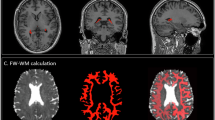

CP and CSF volumes

The lateral ventricular CP volume was manually segmented from 3D T1-weighted volumetric images using ITK-SNAP software (version 4.0)(see Fig. 1). CSF volume and total intracranial volume (TIV) were calculated using the CAT12 toolkit (http://www.neuro.uni-jena.de/cat/) within SPM12 (https://www.fil.ion.ucl.ac.uk/spm/software/spm12/) in MATLAB R2022b (MathWorks). To adjust for inter-participant variability, CP and CSF volumes were normalized by expressing each as a ratio to TIV, in accordance with established methodology.